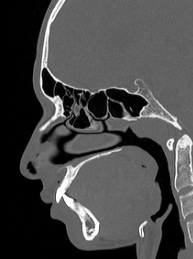

Лицевой череп состоит из крупных костей (верхняя и нижняя челюсти, лобные кости, скуловые кости) и сгруппированных вокруг них остальных мелких костей. При травмах лицевых костей часто наблюдается смещение мелких отломков, которые не видны при обычной рентгенографии. Мультиспиральная компьютерная томография позволяет детально изучить кости лицевого черепа, а также углубления, которые являются вместилищем для важных органов (глазницы, полость носа, ротовая полость).

Метод КТ основан на применении рентгеновского излучения и различной способности тканей поглощать рентгеновские лучи. Костные структуры обладают наибольшей плотностью по сравнению с другими тканями, поэтому в большей степени поглощают рентгеновские лучи и лучше всего визуализируются при данном исследовании.

КТ костей лица является наиболее информативным методом диагностики травм лицевого черепа, посттравматических деформаций, аномалий развития, инородных предметов в носовой полости и околоносовых пазухах. Кроме того, мультиспиральная КТ применяется при воспалительных заболеваниях ЛОР-органов, а также для выявления опухолевых образований доброкачественного и злокачественного характера.

Детальные изображения костей лицевого черепа получаются за счет вращения трубки томографа с излучателями рентгеновских лучей вокруг объекта исследования. В аппаратах увеличено количество сверхчувствительных детекторов, позволяющих производить множество послойных снимков с толщиной среза от 0,5 мм, которые затем преобразуются в трехмерные пространственные модели черепа. Такие инновационные возможности аппаратов обеспечивают проведение точной и достоверной диагностики.